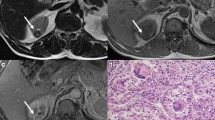

Young age, female sex, and small lesion size are associated with lpAMLs in studies evaluating indeterminate renal lesions. The accuracy of criteria using T2-weighted imaging, diffusion-weighted imaging, chemical shift imaging, dynamic contrast enhancement, multiparametric imaging, and radiomics are reviewed. Low T2 signal intensity is a particularly important MRI feature for lpAML. In studies with low T2 signal intensity, homogeneous early enhancement is a typical feature with an arterial-to-delay enhancement ratio > 1.5. Intratumoral hemorrhage with decrease in signal intensity on in-phase chemical shift imaging may be particularly useful for differentiating papillary renal cell carcinomas from lpAMLs in low T2 signal intensity lesions. Combining clinical and multiparametric MRI features can result in near-perfect specificity for lpAML.